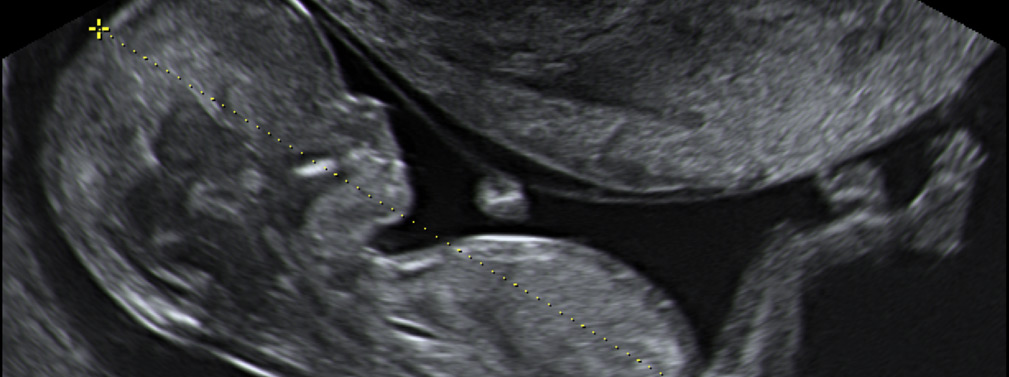

Transvaginal/ginecológicas

Es un examen que utiliza ultrasonidos para obtener imágenes del útero, los ovarios, las trompas de Falopio, el cuello uterino y el área pélvica de la mujer. La ecografía transvaginal también se utiliza como estudio inicial para detectar y controlar el embarazo. Su objetivo es confirmar el diagnóstico de embarazo, revisar la ubicación del embrión, conocer la edad gestacional exacta y saber el número de embriones.

Scan fetal 1° trimestre

(translucencia nucal)La ecografía de la semana 12 de embarazo es un examen que evalúa el crecimiento y la biometría fetal. Esta prueba es una estimación matemática que calcula el riesgo que tiene el bebé de padecer alteraciones cromosómicas, como la trisomía 21 (Síndrome de Down) y la trisomía 18 (Síndrome de Edwards).

En la ecografía de la semana 12 de embarazo se puede:

Revisar el engrosamiento del pliegue de la nuca del feto.

Conocer la edad gestacional.

Distinguir con claridad la cabeza, el tórax, el abdomen y las extremidades.

Visualizar la osificación del hueso nasal, el Doppler de la válvula tricúspide y del conducto venoso (Ductus).